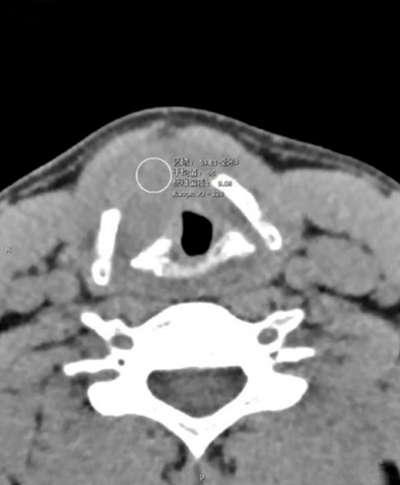

声门层面右侧声带增厚,呈结节状软组织密度影,边界尚可见,前联合及左侧声带前1/2受累,声门左偏,周围脂肪间隙小时,右侧甲状软骨骨质破坏。增强扫描呈轻度延迟强化。